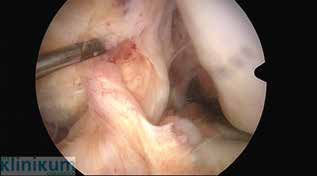

Bei zusätzlichen traumatischen Meniskusrupturen, die rekonstruierbar sind, sollten diese bei Sportlern refixiert werden. Die Refixation sollte mit der Rekonstruktion des vorderen Kreuzbandes verbunden werden. Die konservative Therapie der vorderen Kreuzbandverletzung erfolgt mit einem muskulären Kräftigungsprogramm und sensomotorischem Training. Das sportliche Aktivitätsniveau wird angepasst. Der Erfolg der Therapie muss regelmäßig überprüft werden. Bei „Givingway-Phänomen“ und hoher Aktivität wird zur Verhinderung von Meniskus- und Knorpelschäden bei chronischen Instabilitäten zur operativen Versorgung geraten. Wissenschaftliche Arbeiten haben gezeigt, dass nicht das Lebensalter, sondern die Aktivität Sekundärschäden bei Kreuzbandinstabilität begünstigt 4. Die Indikation zur operativen Versorgung besteht auch beim älteren Sportler, wenn er durch Giving-way-Phänomene im Sport oder im täglichen Leben beeinträchtigt ist. Eine bereits fortgeschrittene Kniearthrose stellt dagegen eine Kontraindikation für einen Bandersatz dar. Die vordere Kreuzbandrekonstruktion wird heute in arthroskopischer Versorgungstechnik durchgeführt. Frische Verletzungen können mit einer primären Ersatzplastik, einer transossären Re-Insertion bei gleichzeitiger Augmentation (bei femoralem Abriss) oder mit einer knöchernen Refixation bei knöchernem Eminentiaausriss versorgt werden. Im deutschsprachigen Raum werden als häufigste Transplantate die Semitendinosus-/Gracilissehne, das mittlere Drittel der Patellarsehne oder ein Quadrizepssehnenanteil verwendet (Abb. 2). Die Transplantatwahl richtet sich nach den individuellen Bedürfnissen des Sportlers, der Sportart, dem Beruf und den körperlichen Gegebenheiten. Ziel ist eine möglichst anatomiegerechte Rekonstruktion des vorderen Kreuzbandes 5.

Für den Erfolg der Kreuzbandersatzplastik ist eine korrekte Tunnelplatzierung entscheidend. Auf eine impingementfreie Implantation des Bandes ist zu achten. Die Platzierung des femoralen Bohrkanals erfolgt über das anteromediale Zugangsportal bei Flexion des Kniegelenkes über 110°. Die Transplantatfixation erfolgt gelenknah mit bioresorbierbaren Interferenzschrauben oder gelenkfern mit Buttons (Abb. 3). Durch die Beschreibung des Aufbaus des vorderen Kreuzbandes mit seiner flachen/rechteckigen femoralen und flachen c‑förmigen tibialen Insertion durch Smigielski 6 entwickeln sich mit Hilfe spezieller Zielgeräte neue Operationstechniken.